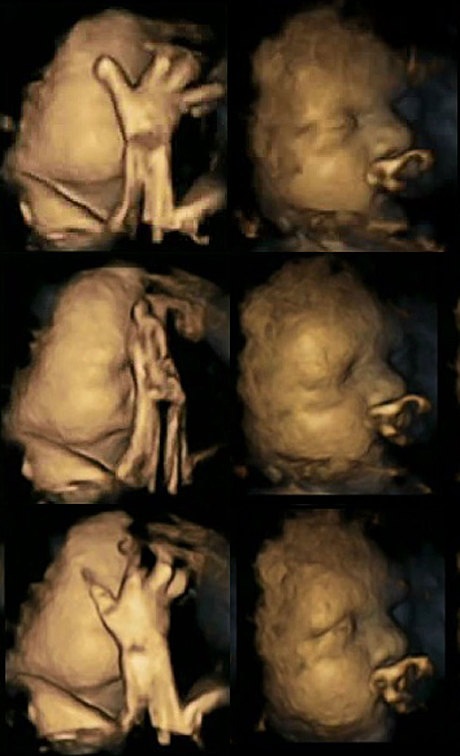

Thai nhi nằm trong bụng một người mẹ đang hút thuốc (trái) có dấu hiệu chuyển động miệng liên tục và đưa tay lên vuốt mặt nhiều đáng kể so với thai nhi nằm trong tử cung một người mẹ không hút thuốc (phải).

Thai nhi trong bụng người mẹ hút hơn 14 điếu thuốc mỗi ngày (trái) so với hình ảnh thai nhi trong bụng bà mẹ không hút thuốc.

Sau khi nghiên cứu hình ảnh quét của thai nhi lúc 24, 28, 32 và 36 tuần, Nadja nhận thấy rằng thai nhi trong bụng những người mẹ hút thuốc thường xuyên cử động miệng và đưa tay chạm vào cơ thể. Điều này không xuất hiện ở các bé có mẹ không hút thuốc.